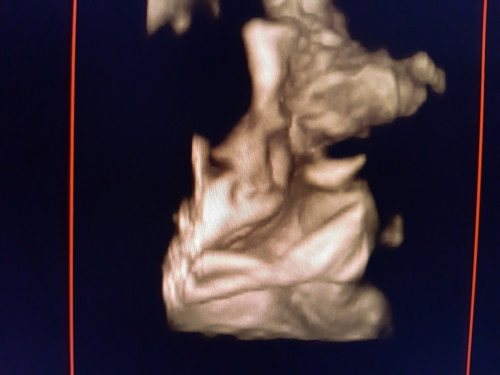

Pas hamil 38 wekk aku sering keputihan bun ituu wajar gak sihhh ..